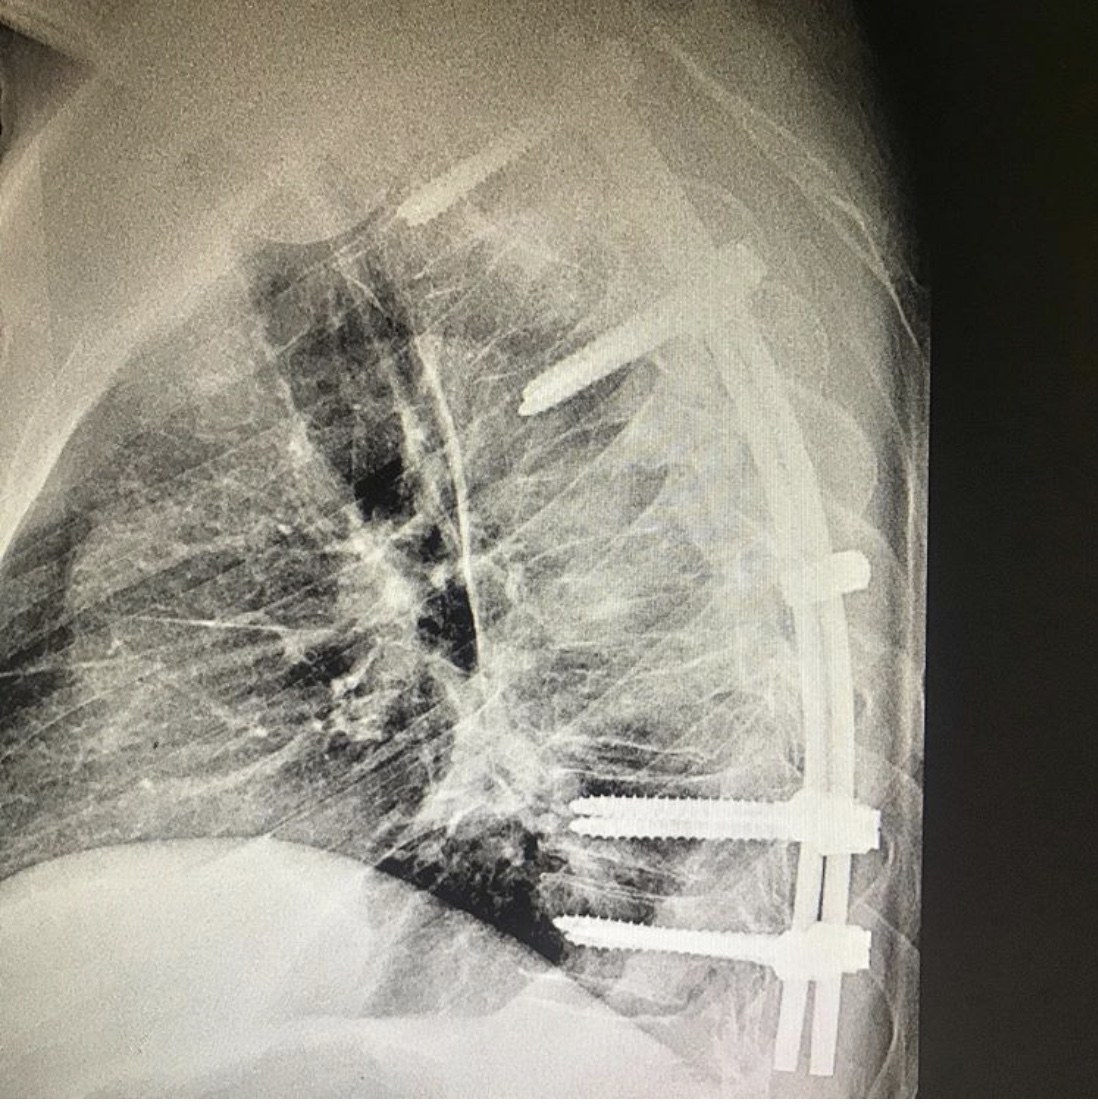

Пациент с нестабильным переломом грудных позвонков, с переломом суставных отростков был экстренно доставлен в Городскую клиническую больницу № 7 Казани. Как сообщает врач – травматолог – ортопед клиники Руслан Ильгизарович Закиров, переломы в данном отделе опасны своими тяжелыми осложнениями, которые представляют угрозу для жизни пациента. Особенно, если они единовременно сочетаются с дополнительными поражениями связок, хрящей, мышц, спинного мозга, нервных структур, кровеносных сосудов и внутренних органов.

После тщательного обследования пациенту была выполнена реклинация и задняя стабилизация транспедикулярной системой: транспедикулярный спондилодез Д3-Д10.